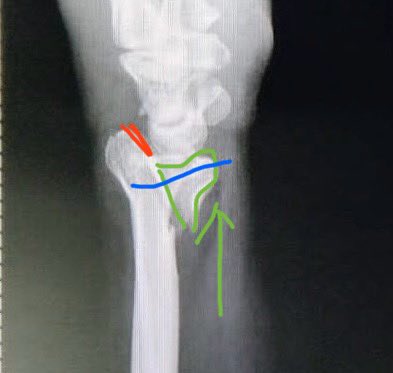

Volar plate would fix this.

1- Green. Reducing this to gain volar length & joint reduction is easy with volar plate

2- Blue. If there is a split at/just below the Teardrop/ watershed, should rather use a Rim plate.

3- Red. Impacted dorsal joint reduction is challenging.

45y male, what is your plan of reduction and fixation? P.S: don't have a CT.@DrBhavinJadav @FractureDoc @InvictaOrtho #orthotwitter @

45y male, what is your plan of reduction and fixation?

P.S: don't have a CT.@DrBhavinJadav @FractureDoc @InvictaOrtho #orthotwitter